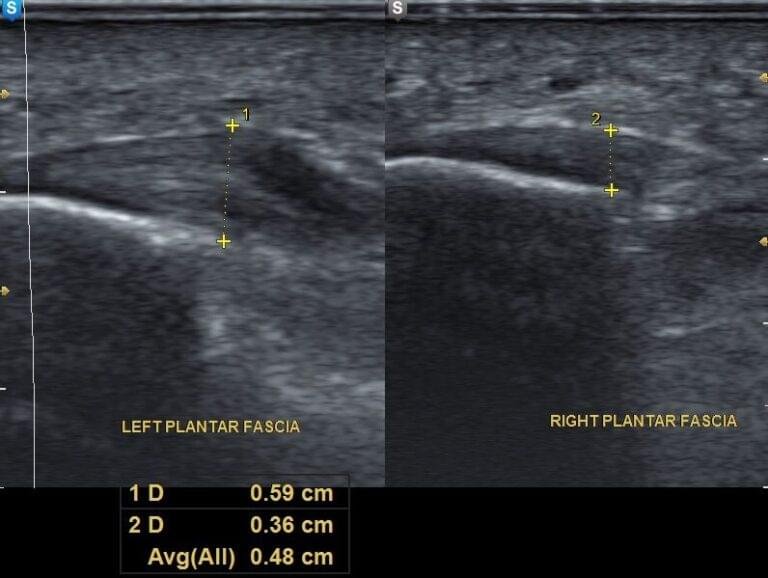

Plantar fasciitis is, in most cases, a clinical diagnosis, and additional imaging studies are not routinely required. However, when the clinical presentation is unclear or when alternative diagnoses are suspected, imaging such as X-ray or ultrasound may be indicated.

Ultrasound is a highly useful diagnostic tool for evaluating soft tissue structures of the foot. It can demonstrate thickening of the plantar fascia, local swelling, and calcifications at its attachment to the calcaneus, as well as monitor changes during treatment.